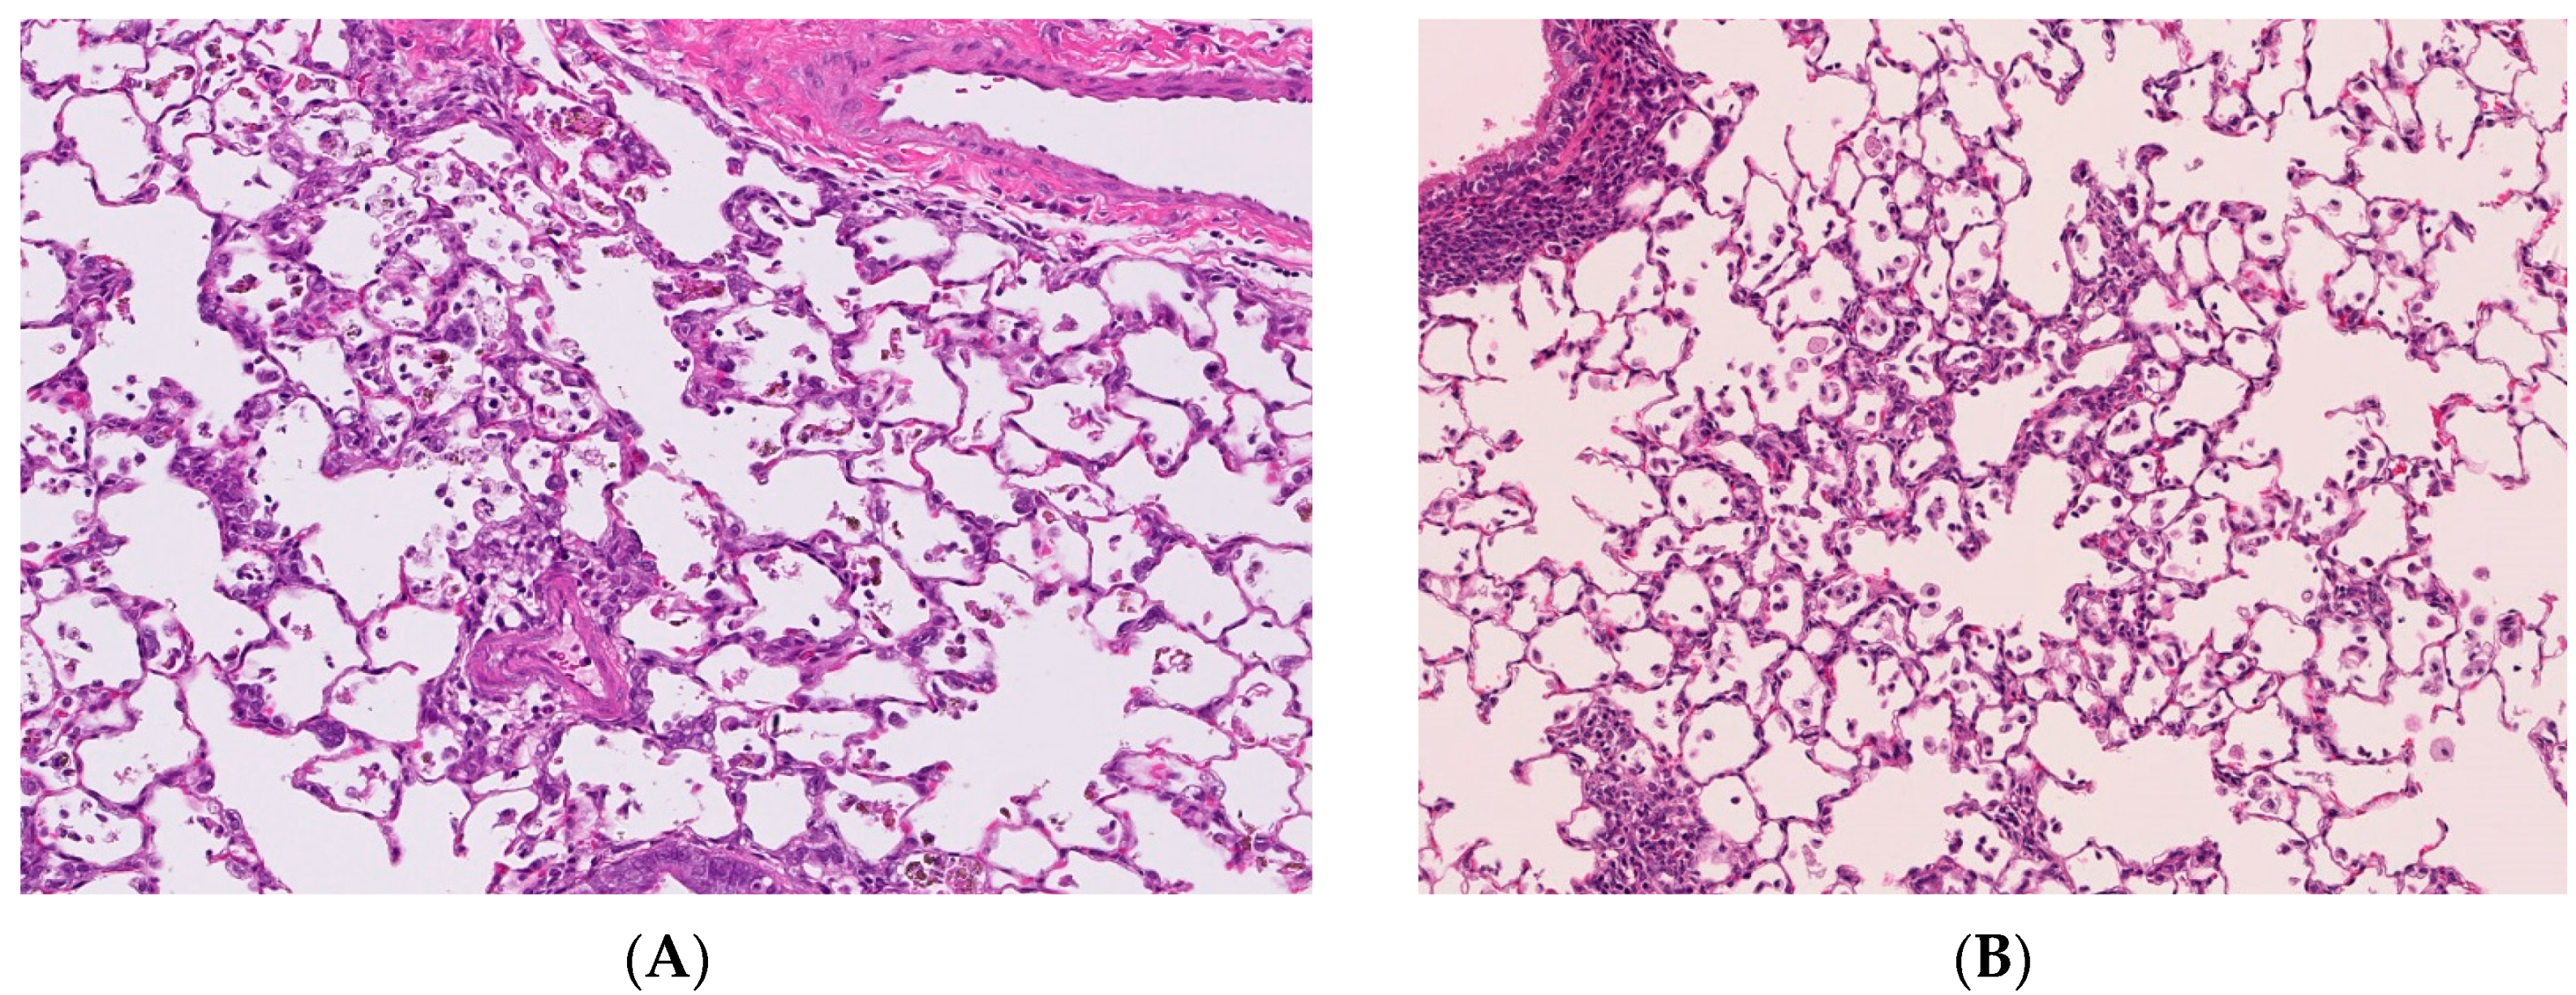

Figure 1. Pathological features of lung tissue in rats after intratracheal instillation of nanoparticles. Magnification 100×. (A) 1mg-crystalline silica-exposed lung at one week; (B) 1mg-TiO2 nanoparticle-exposed lung at one week; (C) 1mg-crystalline silica-exposed lung at six months; (D) 1mg-TiO2 nanoparticle-exposed lung at six months. Pulmonary inflammation in TiO2-exposed lung was more severe than that in crystalline silica-exposed lung at one week following intratracheal instillation. However, pulmonary inflammation in TiO2-exposed lung disappeared at six months and the inflammation in crystalline-exposed lung severely increased.

Some inhalation studies have an observation period of three months in order to observe the recovery from pathological changes [11,12]. The persistence of pathological changes should be similarly observed in intratracheal instillation studies. We performed intratracheal instillations of different mineral fibers to rats and examined lung inflammation from three days to six months [11]. Harmful respirable particles like crystalline silica and crocidolite asbestos, which are kinds of asbestos, caused persistent inflammation from the initial instillation until six months later (Figure 1). Intratracheal exposure of nickel oxide (NiO) nanoparticles induced pulmonary inflammation in rats, and the peak of inflammation was at three months post exposure [10]. Creutzenberg et al. [17] performed an intratracheal instillation study of TiO2 and a positive control made of quartz, and the number of neutrophils in the positive control increased in a time dependent fashion (until 90 days post exposure). On the other hand, when less harmful micron-sized TiO2 was inhaled, only a transient inflammation was observed early in the instillation. Even nanoparticles with low toxicity induce pulmonary inflammation when the observation time is less than one month. Warheit et al. [18] examined the pulmonary inflammation following intratracheal instillation of a variety of TiO2 from 24 h to three months, and there was a TiO2 in which pulmonary inflammation lasted at maximum for one month. Kobayashi et al. [19] showed that different evaluations of pulmonary toxicity by intratracheal instillation of TiO2 nanoparticles can be derived on the basis of observations up to one week post-instillation and those after one month post-instillation. Figure 1 shows pathological features in the lung exposed to respirable chemicals in not only the acute but also the chronic phase. Chemicals with low toxicity induced transient inflammation in the lung in the acute phase (one week), and chemicals with high toxicity induced persistent inflammation in the chronic phase (six months). Considering the persistence of pulmonary inflammation induced by nanoparticles, it is important to evaluate their pulmonary toxicity with a sufficient recovery time of three to six months.